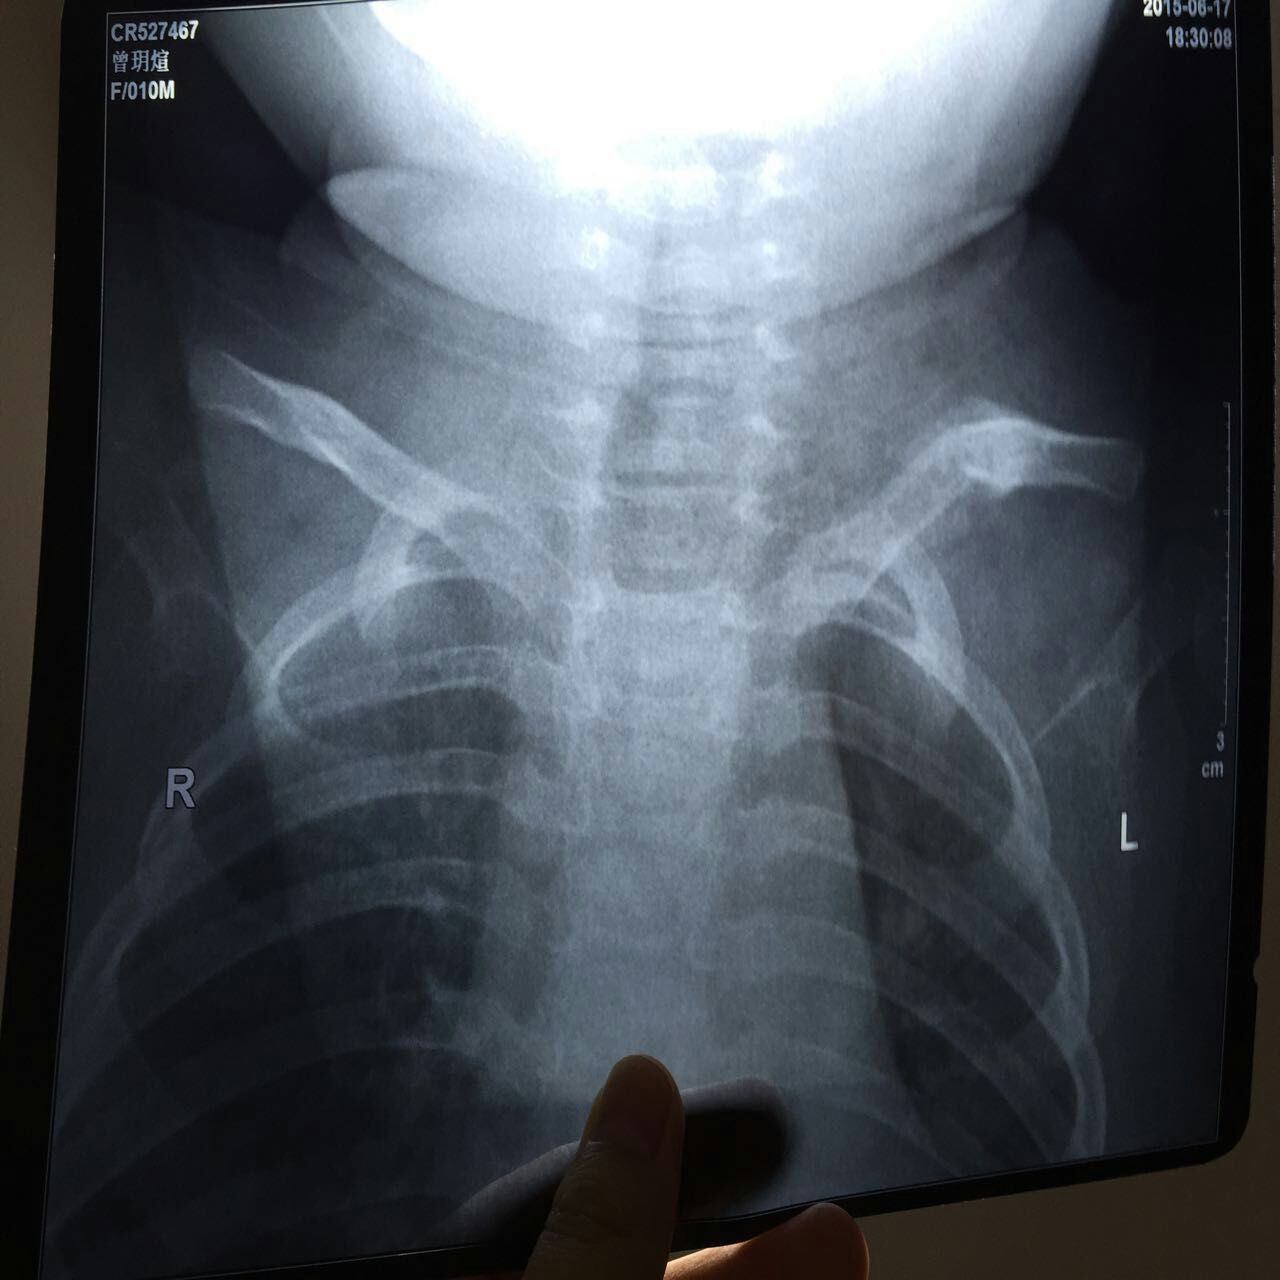

今天发现宝宝一边的锁骨异常突出,带她去医院拍了x光片,医生说是陈旧性骨折,说已经愈合了。自己摸了下宝宝的锁骨,原本一直条的锁骨感觉折度都有35度角以上了,很担心以后越长越弯。会不会给她带来什么影响,现在才九个月大。